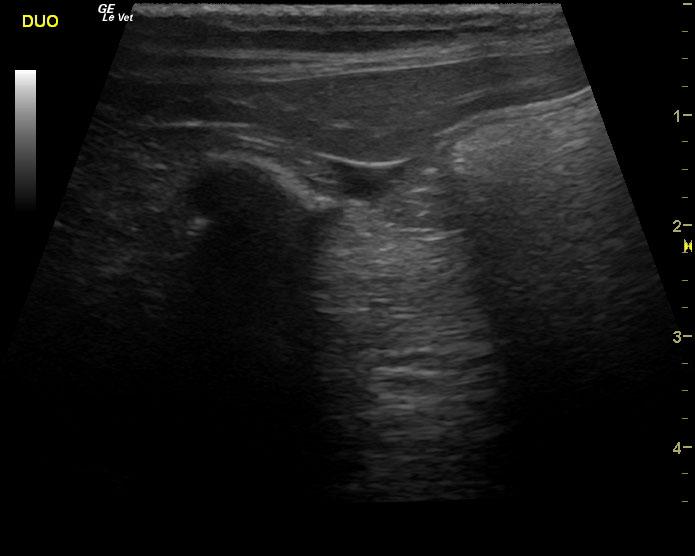

An 18-year-old MN DMH was presented for evaluation of intermittent vomiting and anorexia. A possible abdominal mass was present on abdominal palpation. 1+ calcium oxalate crystals were present on urinalysis. Abnormalities on CBC and serum biochemistry were leukocytosis and hypoproteinemia. T4 was within normal range. Radiographs were within normal limits